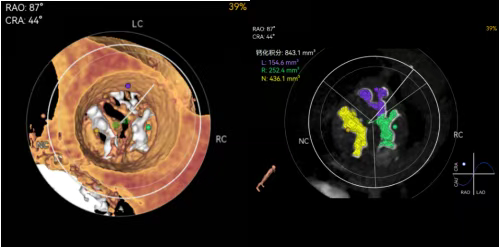

重度主动脉瓣狭窄的常规手术治疗方式有两种,一是传统的外科开胸手术,创伤较大、恢复周期长;二是经导管主动脉瓣置换术(TAVR),属于微创介入治疗,仅通过体表小于1厘米的切口即可完成瓣膜置换,具有创伤小、术后恢复快的优势。经综合评估,该患者为Type1型二叶式主动脉瓣,瓣叶钙化严重,具备良好的锚定条件,冠脉阻挡风险低,且股动脉入路适宜,团队最终决定施行TAVR手术。

图示:主动脉瓣CT重建影像,白色高亮团块为钙化,钙化量高达843mm3